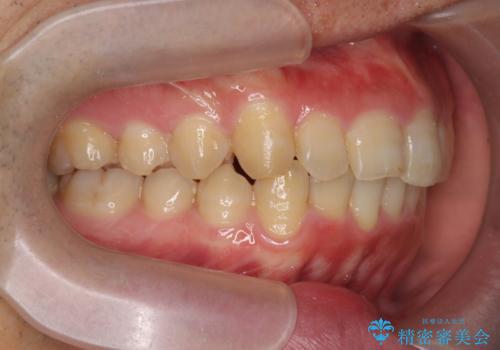

ガタつきの大きい前歯 インビザラインによるマウスピース矯正治療

- ガタつきの目立つ前歯の改善を求めて来院されました。

上顎前突、がたつきを改善すべく上顎臼歯の後方移動・ディスキングを行い歯並びの改善を計画します。

食事・歯ブラシ時以外の時間にしっかりとマウスピースを装着していただけたのでガタつきは大きく改善し良好な歯並びを得ることができました。